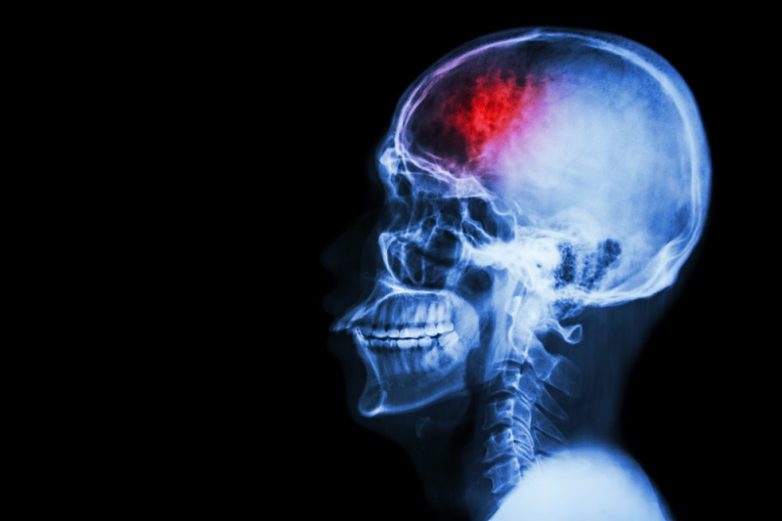

Инсульт — это внезапное нарушение кровообращения головного мозга. Инсульт может наступать из-за спазма, закупорки или разрыва одного из сосудов головного мозга. Раньше инсульт поражал людей старше 60 лет. Сейчас эта проблема стремительно молодеет.